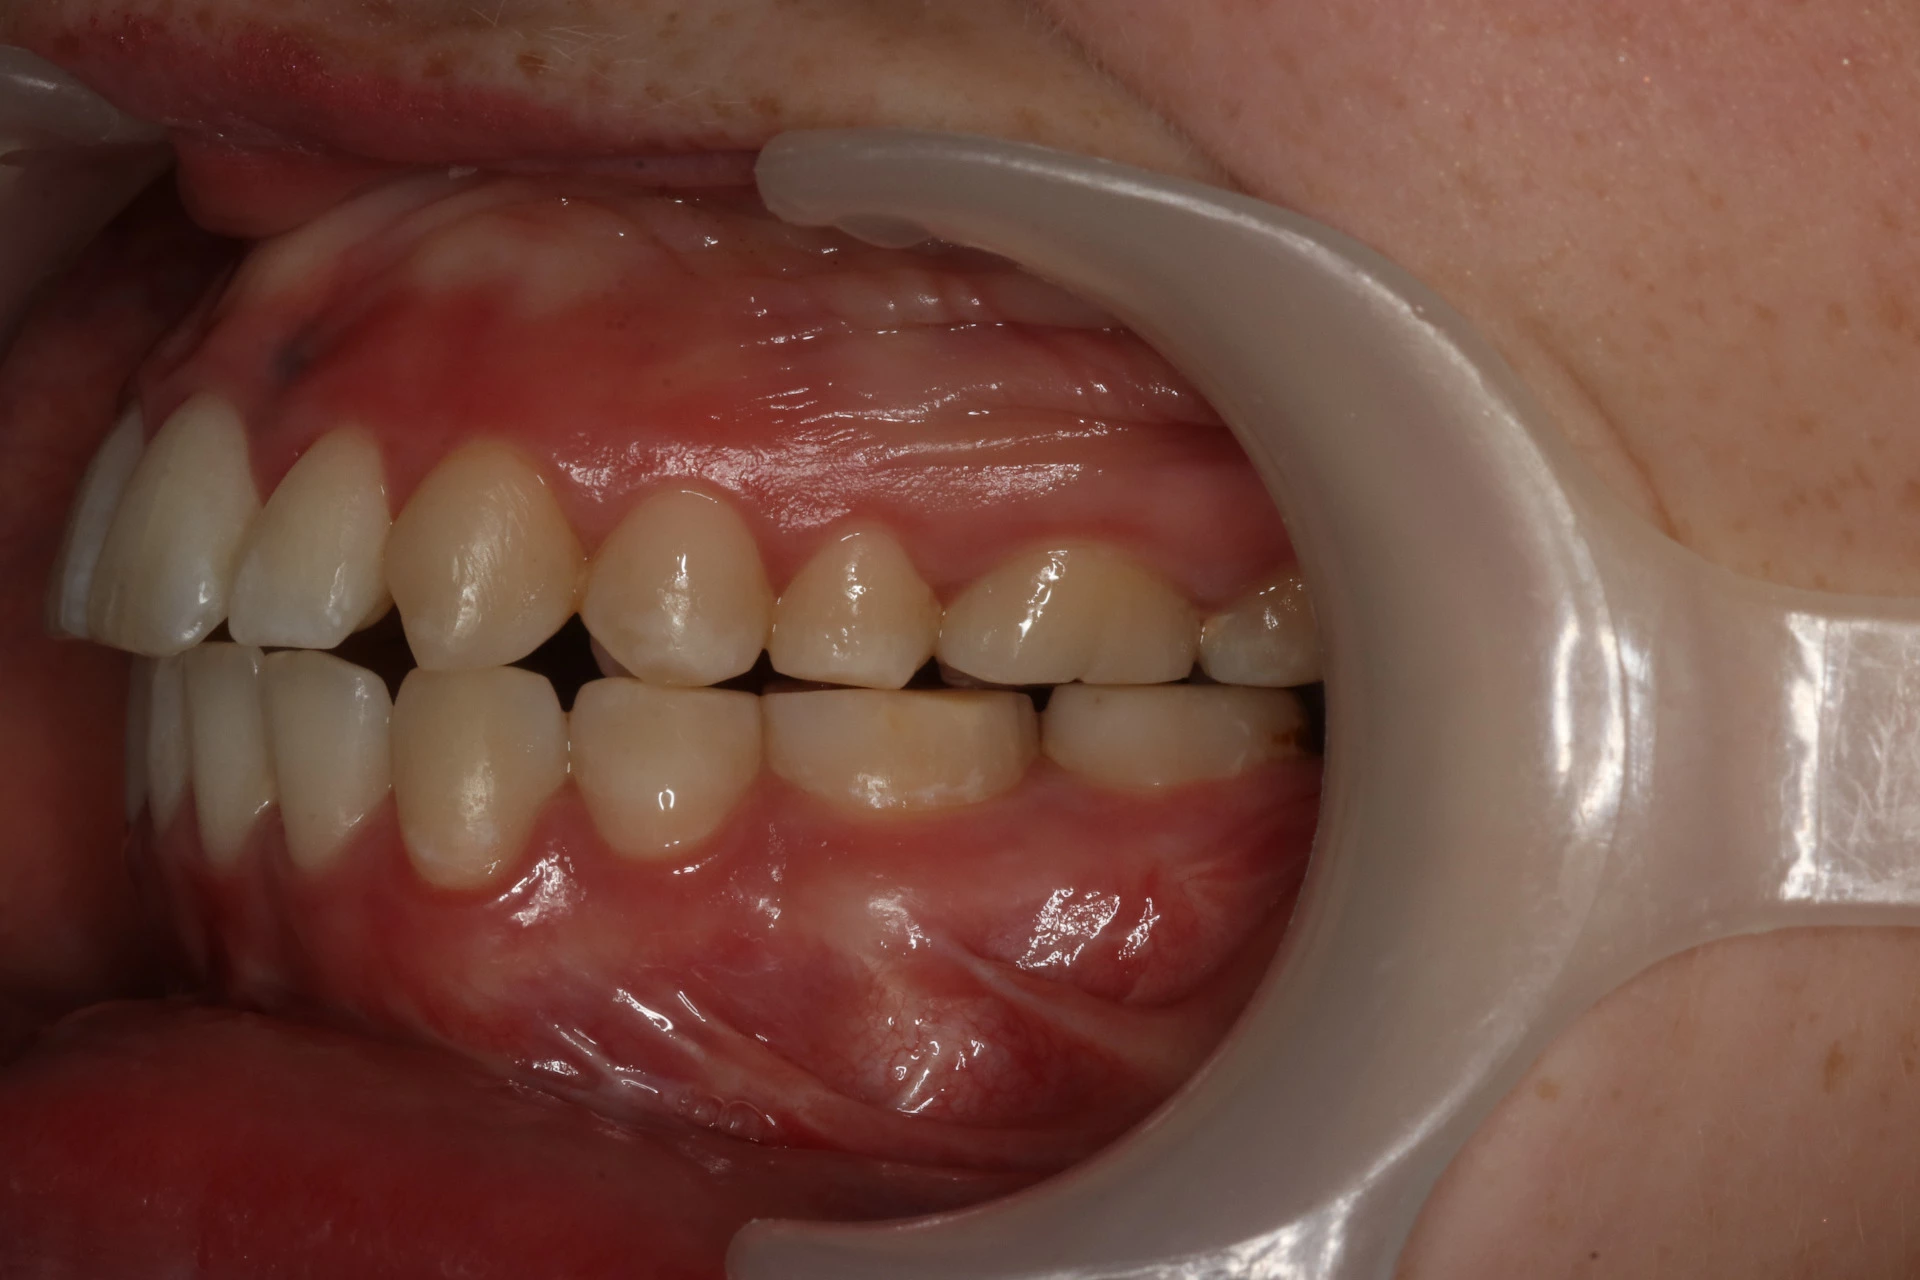

Vårt arbeid

Alle pasienter som vises har gitt skriftlig samtykke til at bildene kan brukes på klinikkens nettside.